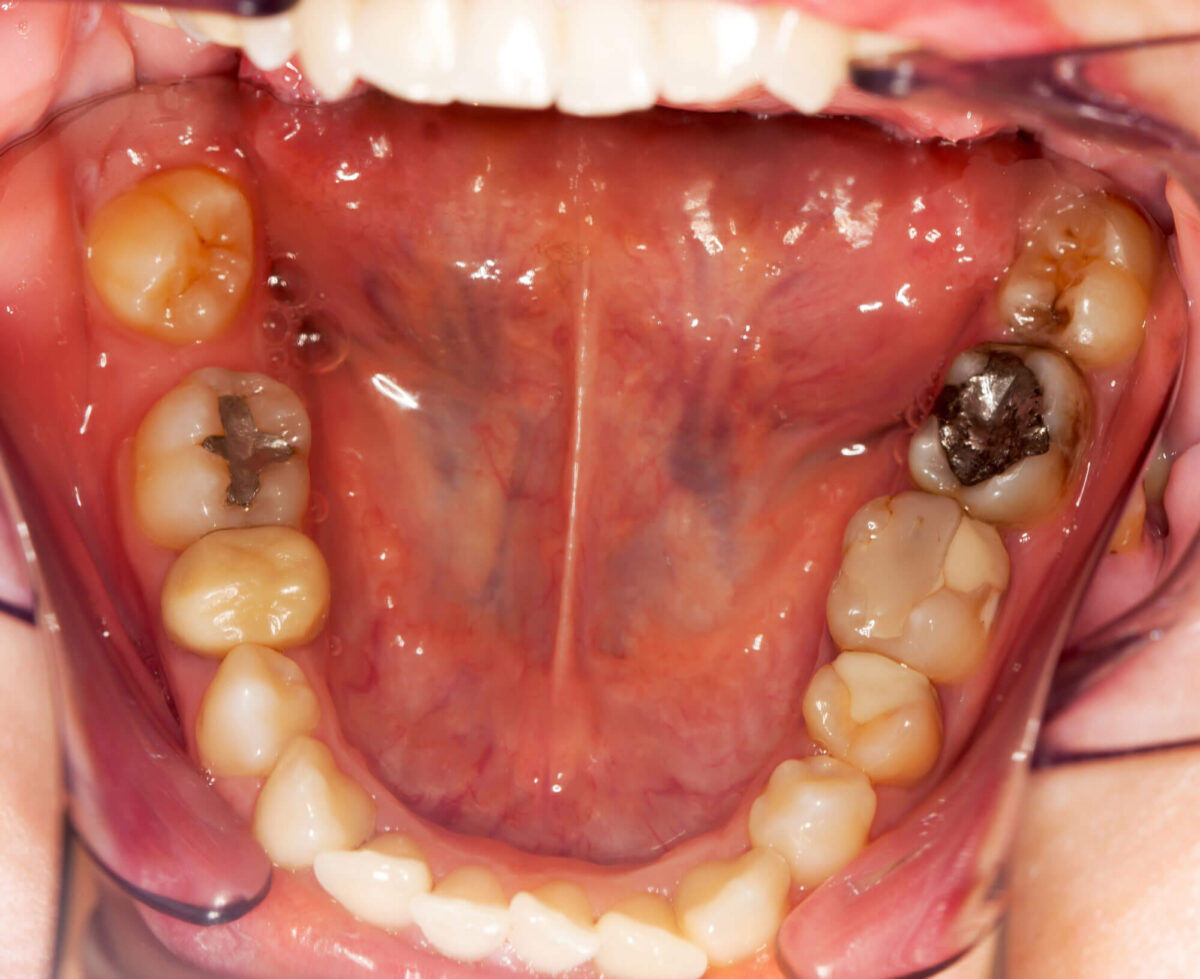

Amalgam is an older type of dental filling that has been around for many years. It is a metal mix that stands up well to chewing. For back teeth that grind and crush food, amalgam handles pressure with little fuss. It is usually less costly and can last many years with simple care. The downside is colour. Amalgam does not match tooth enamel. For a smile that shows when talking, another type of dental filling might be preferred. Still, when durability is the priority, amalgam often fits.

Composite resin fillings are popular. The colour matches the tooth closely. The material bonds to enamel rather than relying only on shape. That often allows more of the original tooth to remain, helping with strength and a natural look. Composites are often chosen for front teeth where appearance matters. They cost more than amalgam in many places and can wear faster on heavy chewing surfaces. For small to medium cavities and for visible teeth, composite is a common answer among types of dental fillings explained to patients.